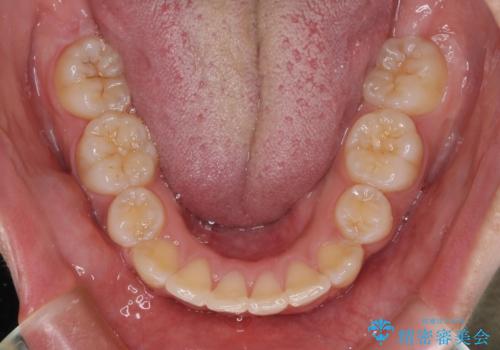

歯列はきれいに整いますが、歯肉ラインは治療前の歯肉の位置を踏襲します。

特に八重歯であった歯は歯冠が長く見えますので、改善を希望される場合には、歯肉移植術を行う必要があります。